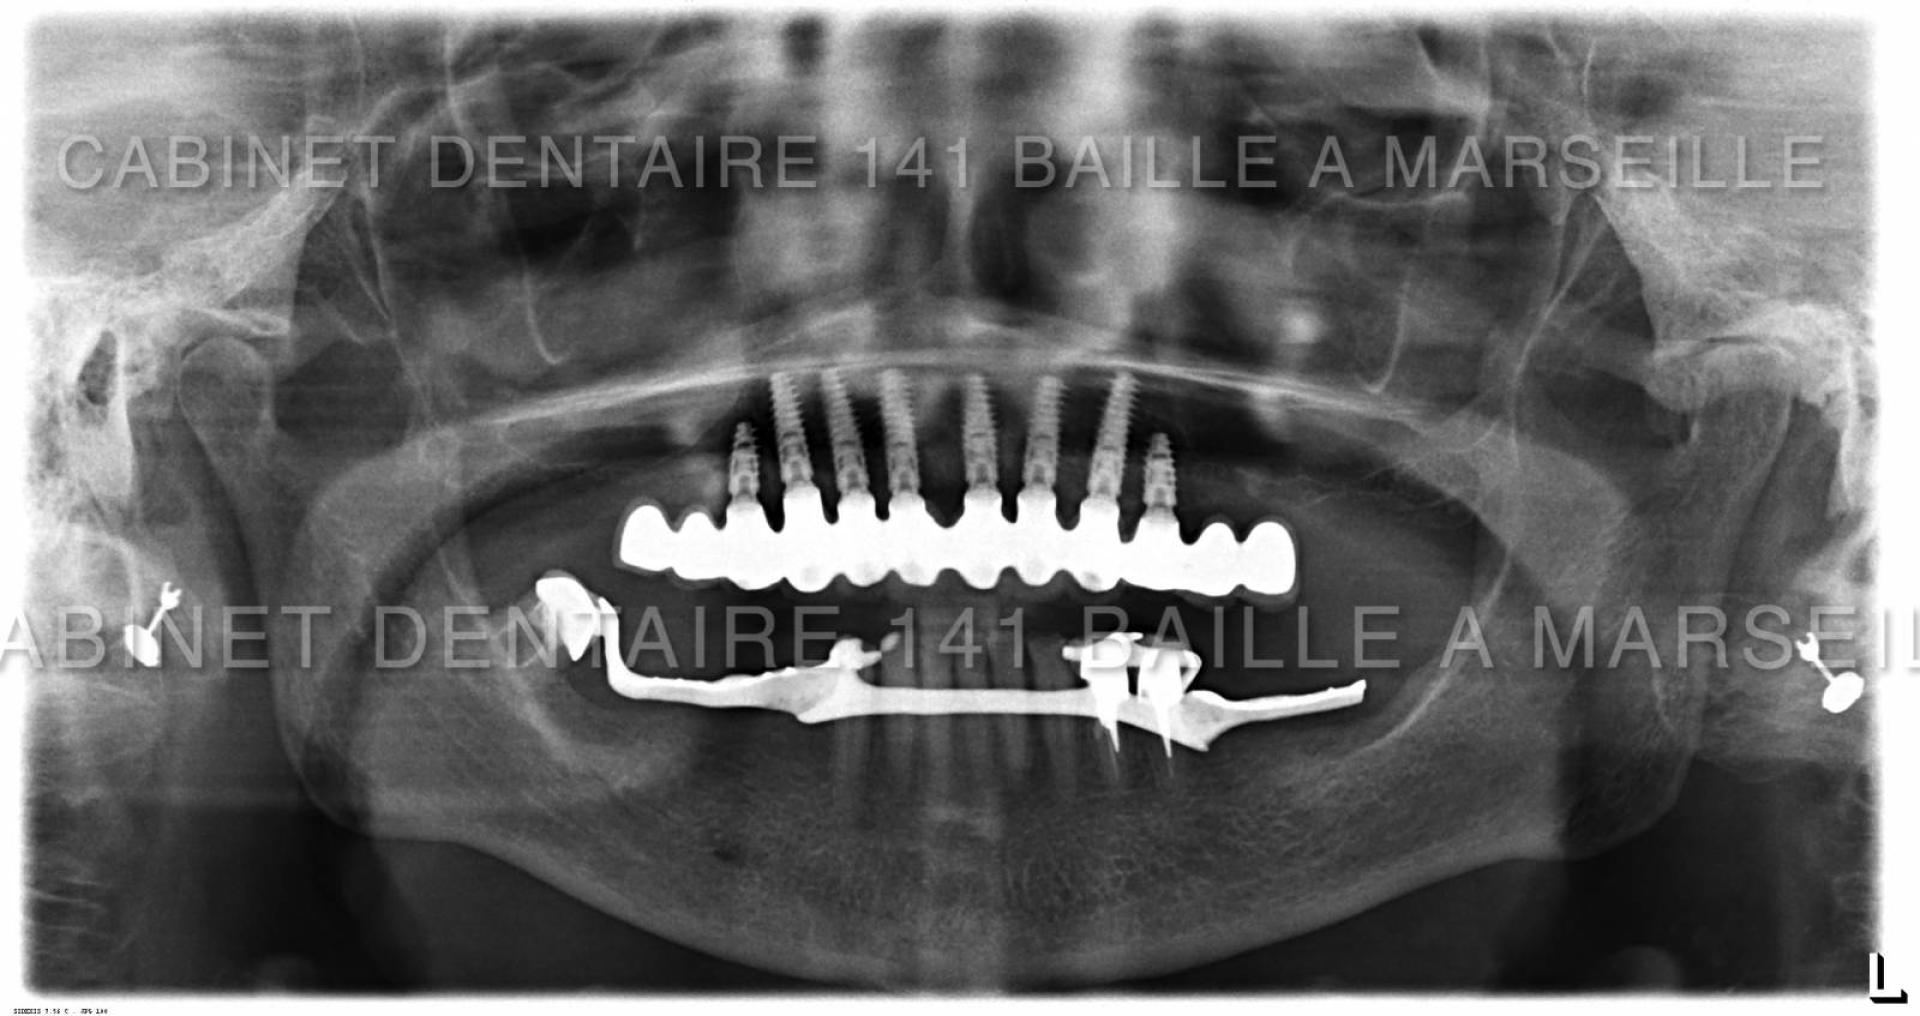

Il peut arriver qu'un patient soit obligé de remplacer toutes ses dents par des implants  dans certains cas de maladies de gencives très agressives qui entrainent une destruction de l'os support des dents .

De nos jours il est possible pour ces patients d'avoir recours à des techniques implantaires appelées implantation complète en général effectuées dans la meme journée .On appelle cette technique la technique d'implantation complète avec mise en charge immédiate (MCI).

Ces techniques necessitent toutefois un chirurgien implantologiste qualifié et formé à ces techniques de mise en charge immédiate,d'un plateau technique complet avec bloc opératoire stérile ,prothésiste,et personnel d'assistance chirurgical qualifié.